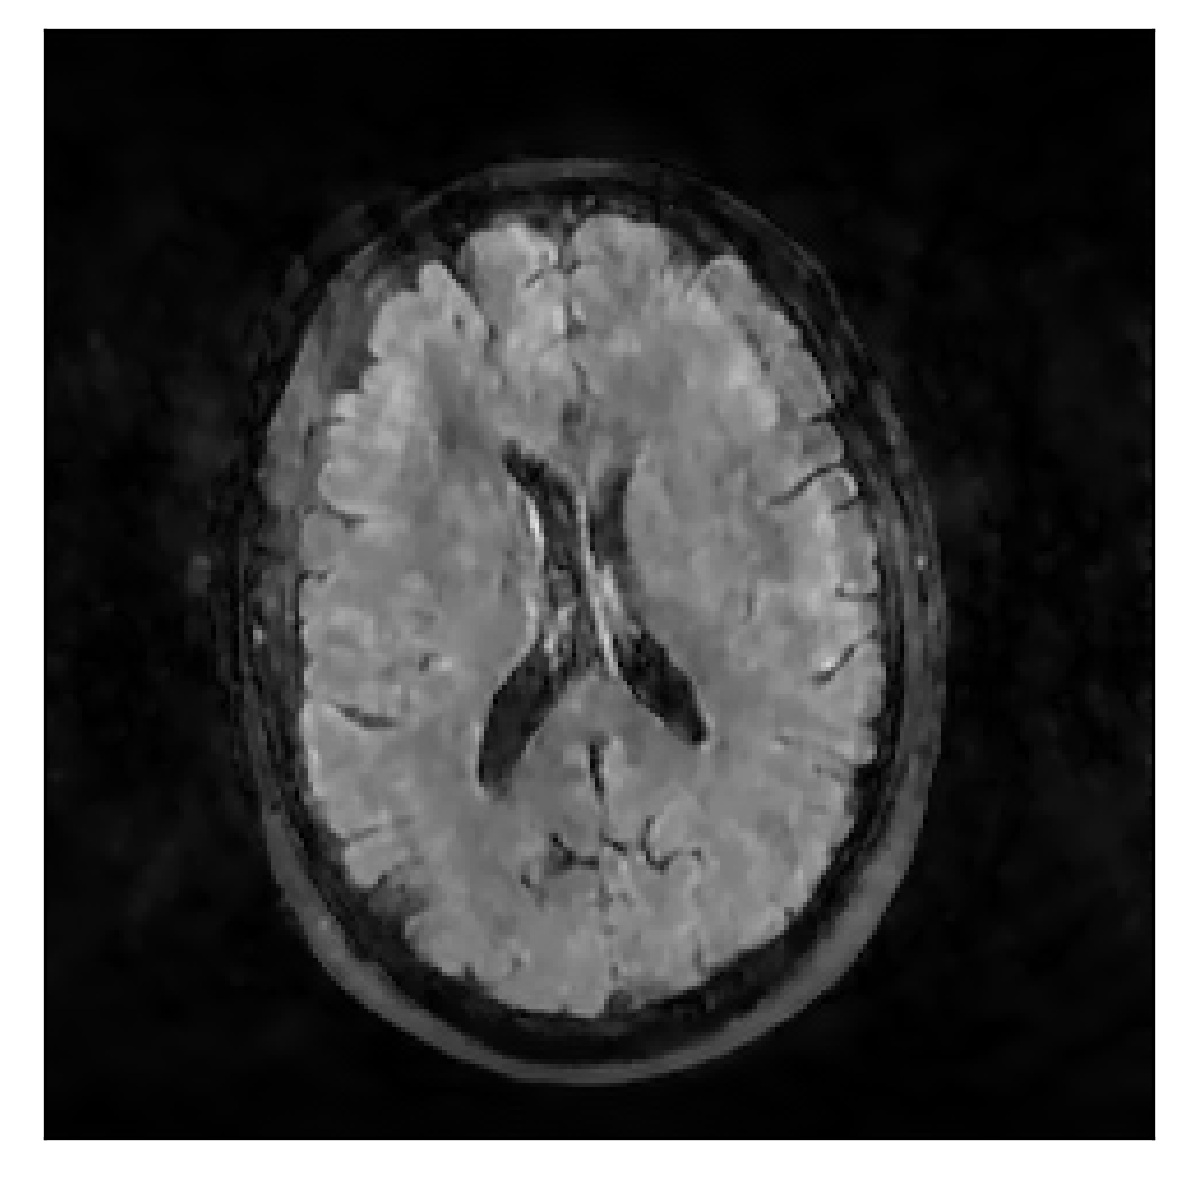

We consider three levels of motion corruption: (i) the volunteer moves once, (ii) the volunteer moves twice, and (iii) the volunteer moves five times. The volunteer is instructed to change its head position every time it is prompted to do so, and maintain that position in between instructions. We use T2-FLAIR-weighted contrasts as corrupted scans, with T1-weighted contrast as a reference (see Table 1 for further details). The corrupted acquisition employs randomized sampling.

4.1 Experiment 1: robustness test

We gather the results for the robustness test described in Section 3.1 (volunteer 1) in Figures 2, 4, and 6 for motion corruption mechanisms associated to one, two, and five changes of position, respectively. Furthermore, we juxtapose the corrected images with varying degrees of corruption in Figure 8. We observe that the proposed method consistently ameliorates the corrupted scan. The quality indexes based on PSNR and SSIM show only a modest decrease in correction quality as a function of motion complexity (Figure 8).

| Section 3.1, Figure 4 | Sagittal | 25.78 | 27.76 | 0.7263 | 0.7816 |

| Coronal | 28.19 | 29.73 | 0.7847 | 0.8244 | |

| Axial | 27.79 | 29.70 | 0.8104 | 0.8362 | |

| Section 3.1, Figure 4 | T2-FLAIR | Completely corrected | Some blurring | No additional artifacts | Good grey white matter differentiation |